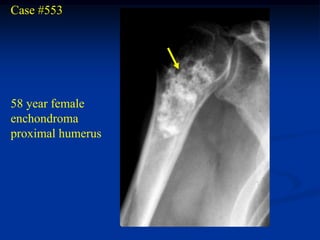

Case #553

58 year female

enchondroma

proximal humerus